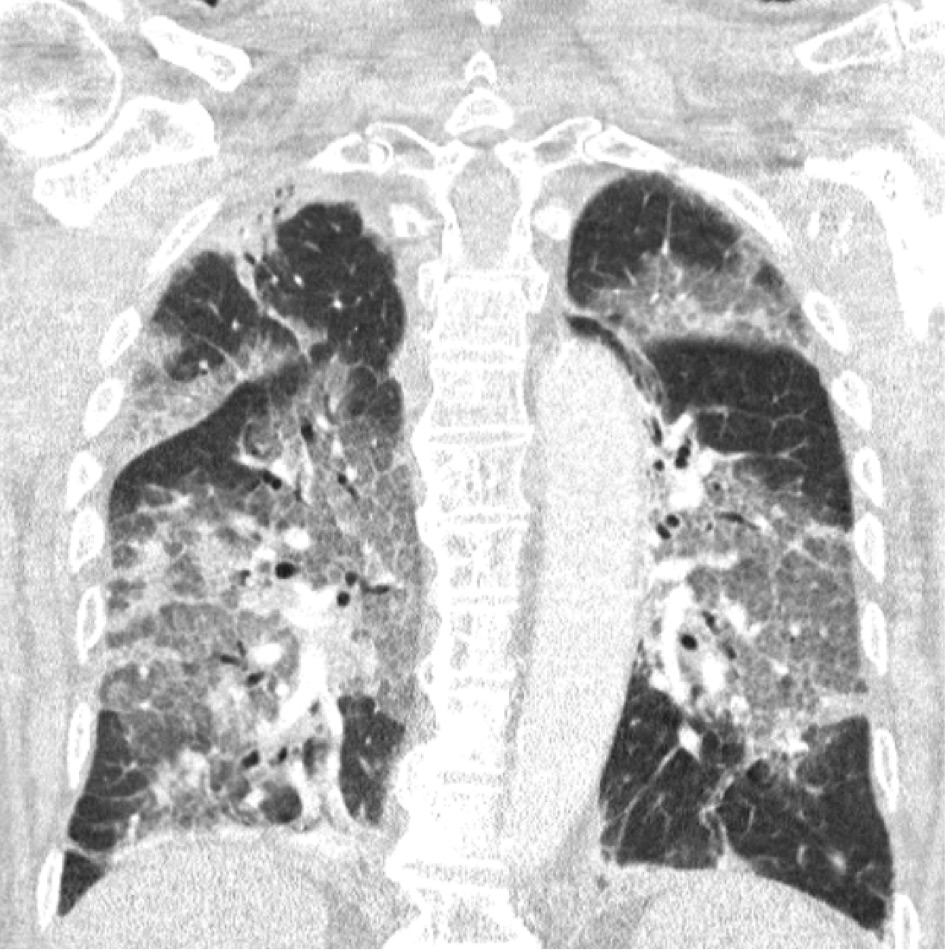

Eerste Nederlandse patiënt valt uit de AstraZeneca-achtbaan. En ziekenhuis Zuyderland slingert een brandbrief plus een foto van twee longen na 13 maanden aan de Hugo online. Het ziekenhuis is zelfs van plan de Astra-prikstop te negeren, en 400 vaccins te geven aan medewerkers onder de 60. Maar goed, de brief.

"Beste minister, leden van de Gezondheidsraad en het RIVM,

Vandaag namen wij de eerste patiënt op in ons ziekenhuis die het Astra-Zeneca-vaccin had geweigerd na alle commotie in de pers. We hoorden de enorme spijt in zijn stem en zagen de wanhoop in zijn ogen. Het virus had hem geveld en dit had wellicht niet gehoeven. Met zijn instemming delen wij hier zijn longscan. Je hoeft geen longarts te zijn om de verwoestingen te herkennen. (...) Beste minister, wij kunnen niet langer wachten. Geen dag langer. Onze IC’s liggen vol met dertigers, veertigers en vijftigers. Door ziekteverzuim en uitputting krijgen we de planning niet meer rond. (...) Wilt u alstublieft stoppen met dralen en onrust zaaien, met insinueren dat u veiligheid biedt door alles eerst goed uit te laten zoeken? De cijfers die de voordelen van massavaccinatie aantonen zijn overweldigend. Ze liegen echt niet. Laten we dan landelijk de maximale vaart erin brengen! Laat mensen zelf de keuze of ze een situatie als die waarin onze patiënt is beland, willen vermijden. (...)."

De betreffende longen

Bron: ziekenhuis Zuyderland